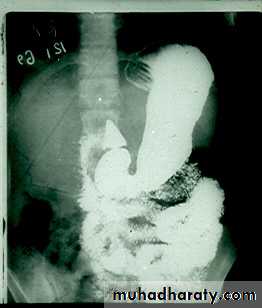

Barium meal is radiological study of esophagus,stomach&duodenum.

Done by oral administration of contrast media”BariumSulphate”

Gastric or duodenal obstruction.

Malignancies of gastroesophagealjunction,stomach&duodenum.

Upper Abdominal mass.

Motility disorders.

Systemic disease like Tb.

GIT hemorrhage.